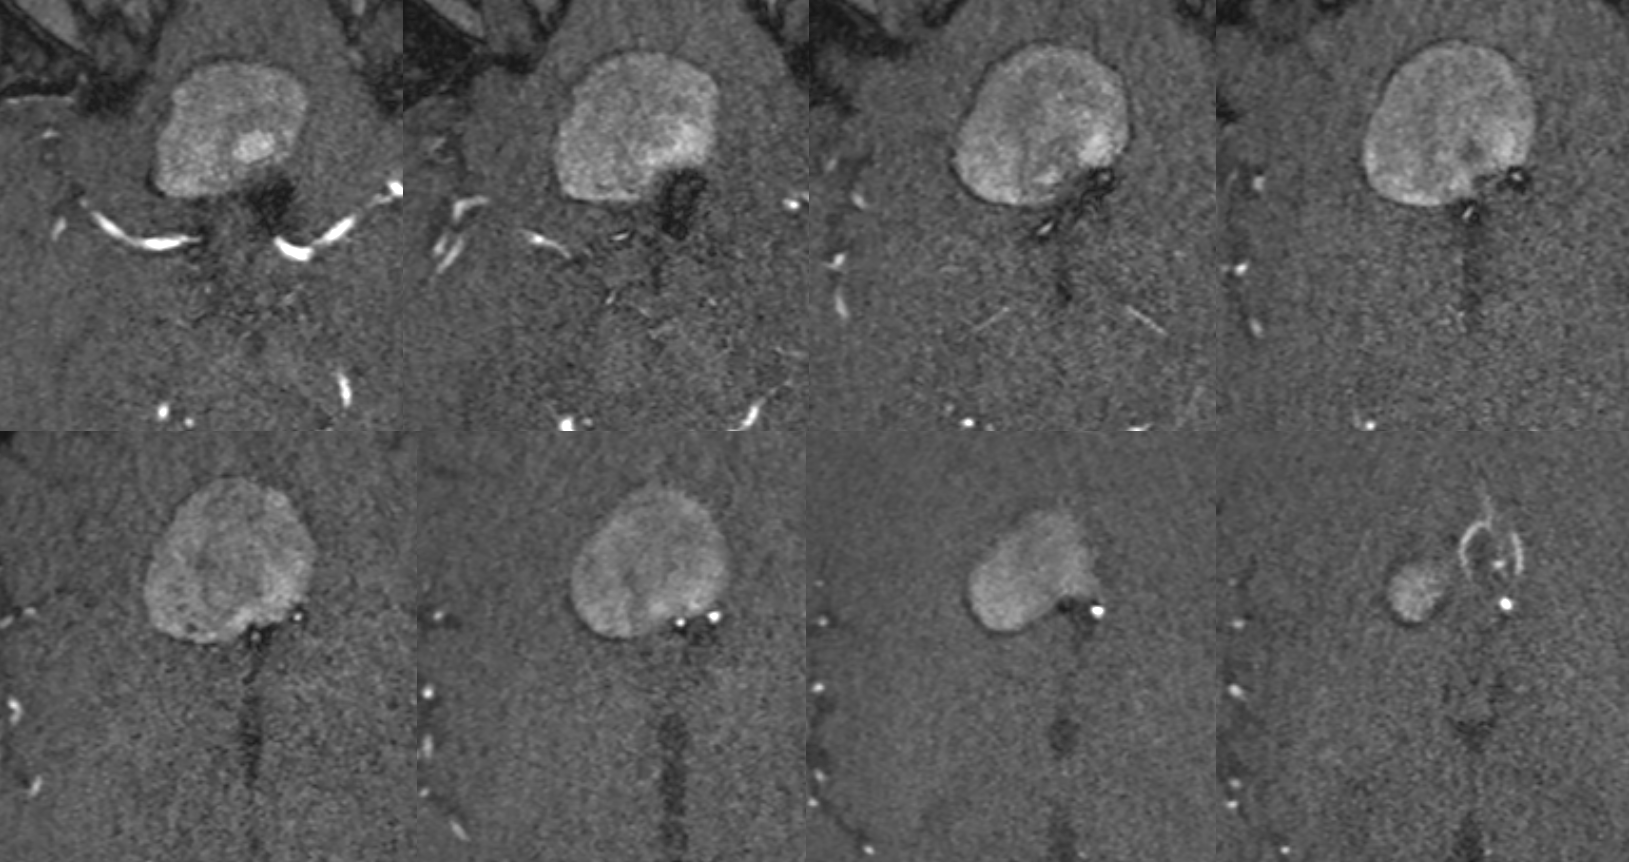

Robust bypass supports superior division and some more

No aneurysm, as suspected

Stereo pairs

Bypasses. Note A3-A3 patent bypass, as well as STA-MCA. Both seen thru radiolucent skull windows